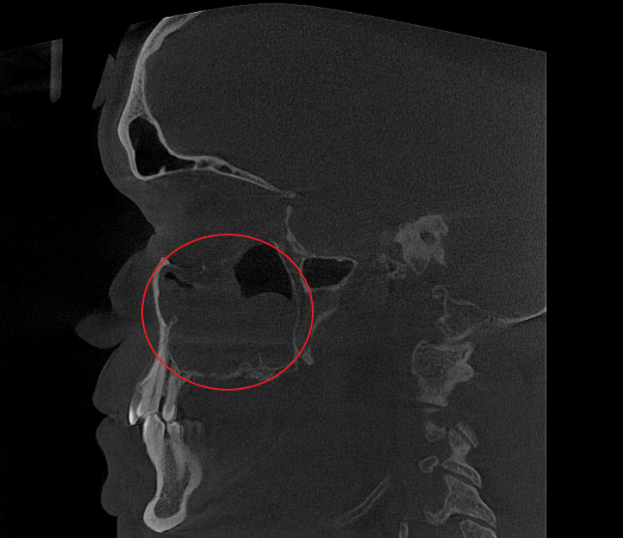

- Компьютерная томография (КЛКТ) околоносовых пазух и височных костей: Этот высокоинформативный метод диагностики объективно показал искривление носовой перегородки вправо, субтотальное снижение пневматизации (воздушности) левой верхнечелюстной пазухи, что свидетельствовало о хроническом воспалительном процессе. Костно-деструктивных изменений не выявлено.

- Хронический левосторонний верхнечелюстной синусит (J32.0). Длительное воспаление слизистой оболочки левой гайморовой пазухи, подтвержденное КТ.